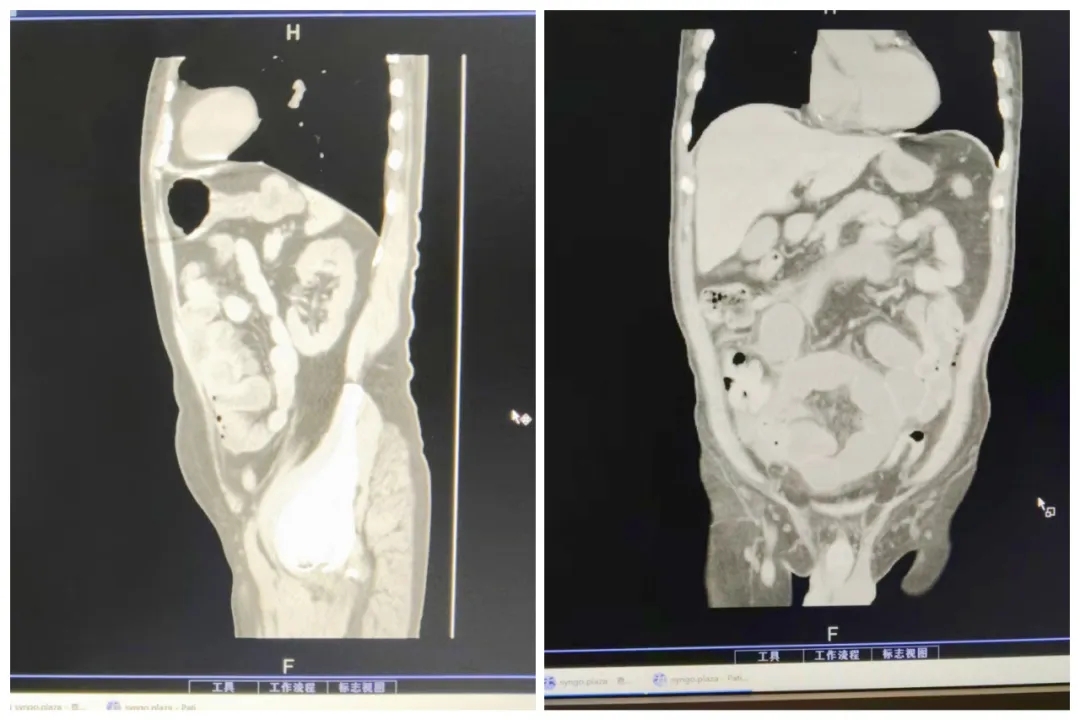

突破高龄禁区 创造生命奇迹 | 河北医大二院急诊外科创新“闸门机理法"成功救治4例90岁以上患者